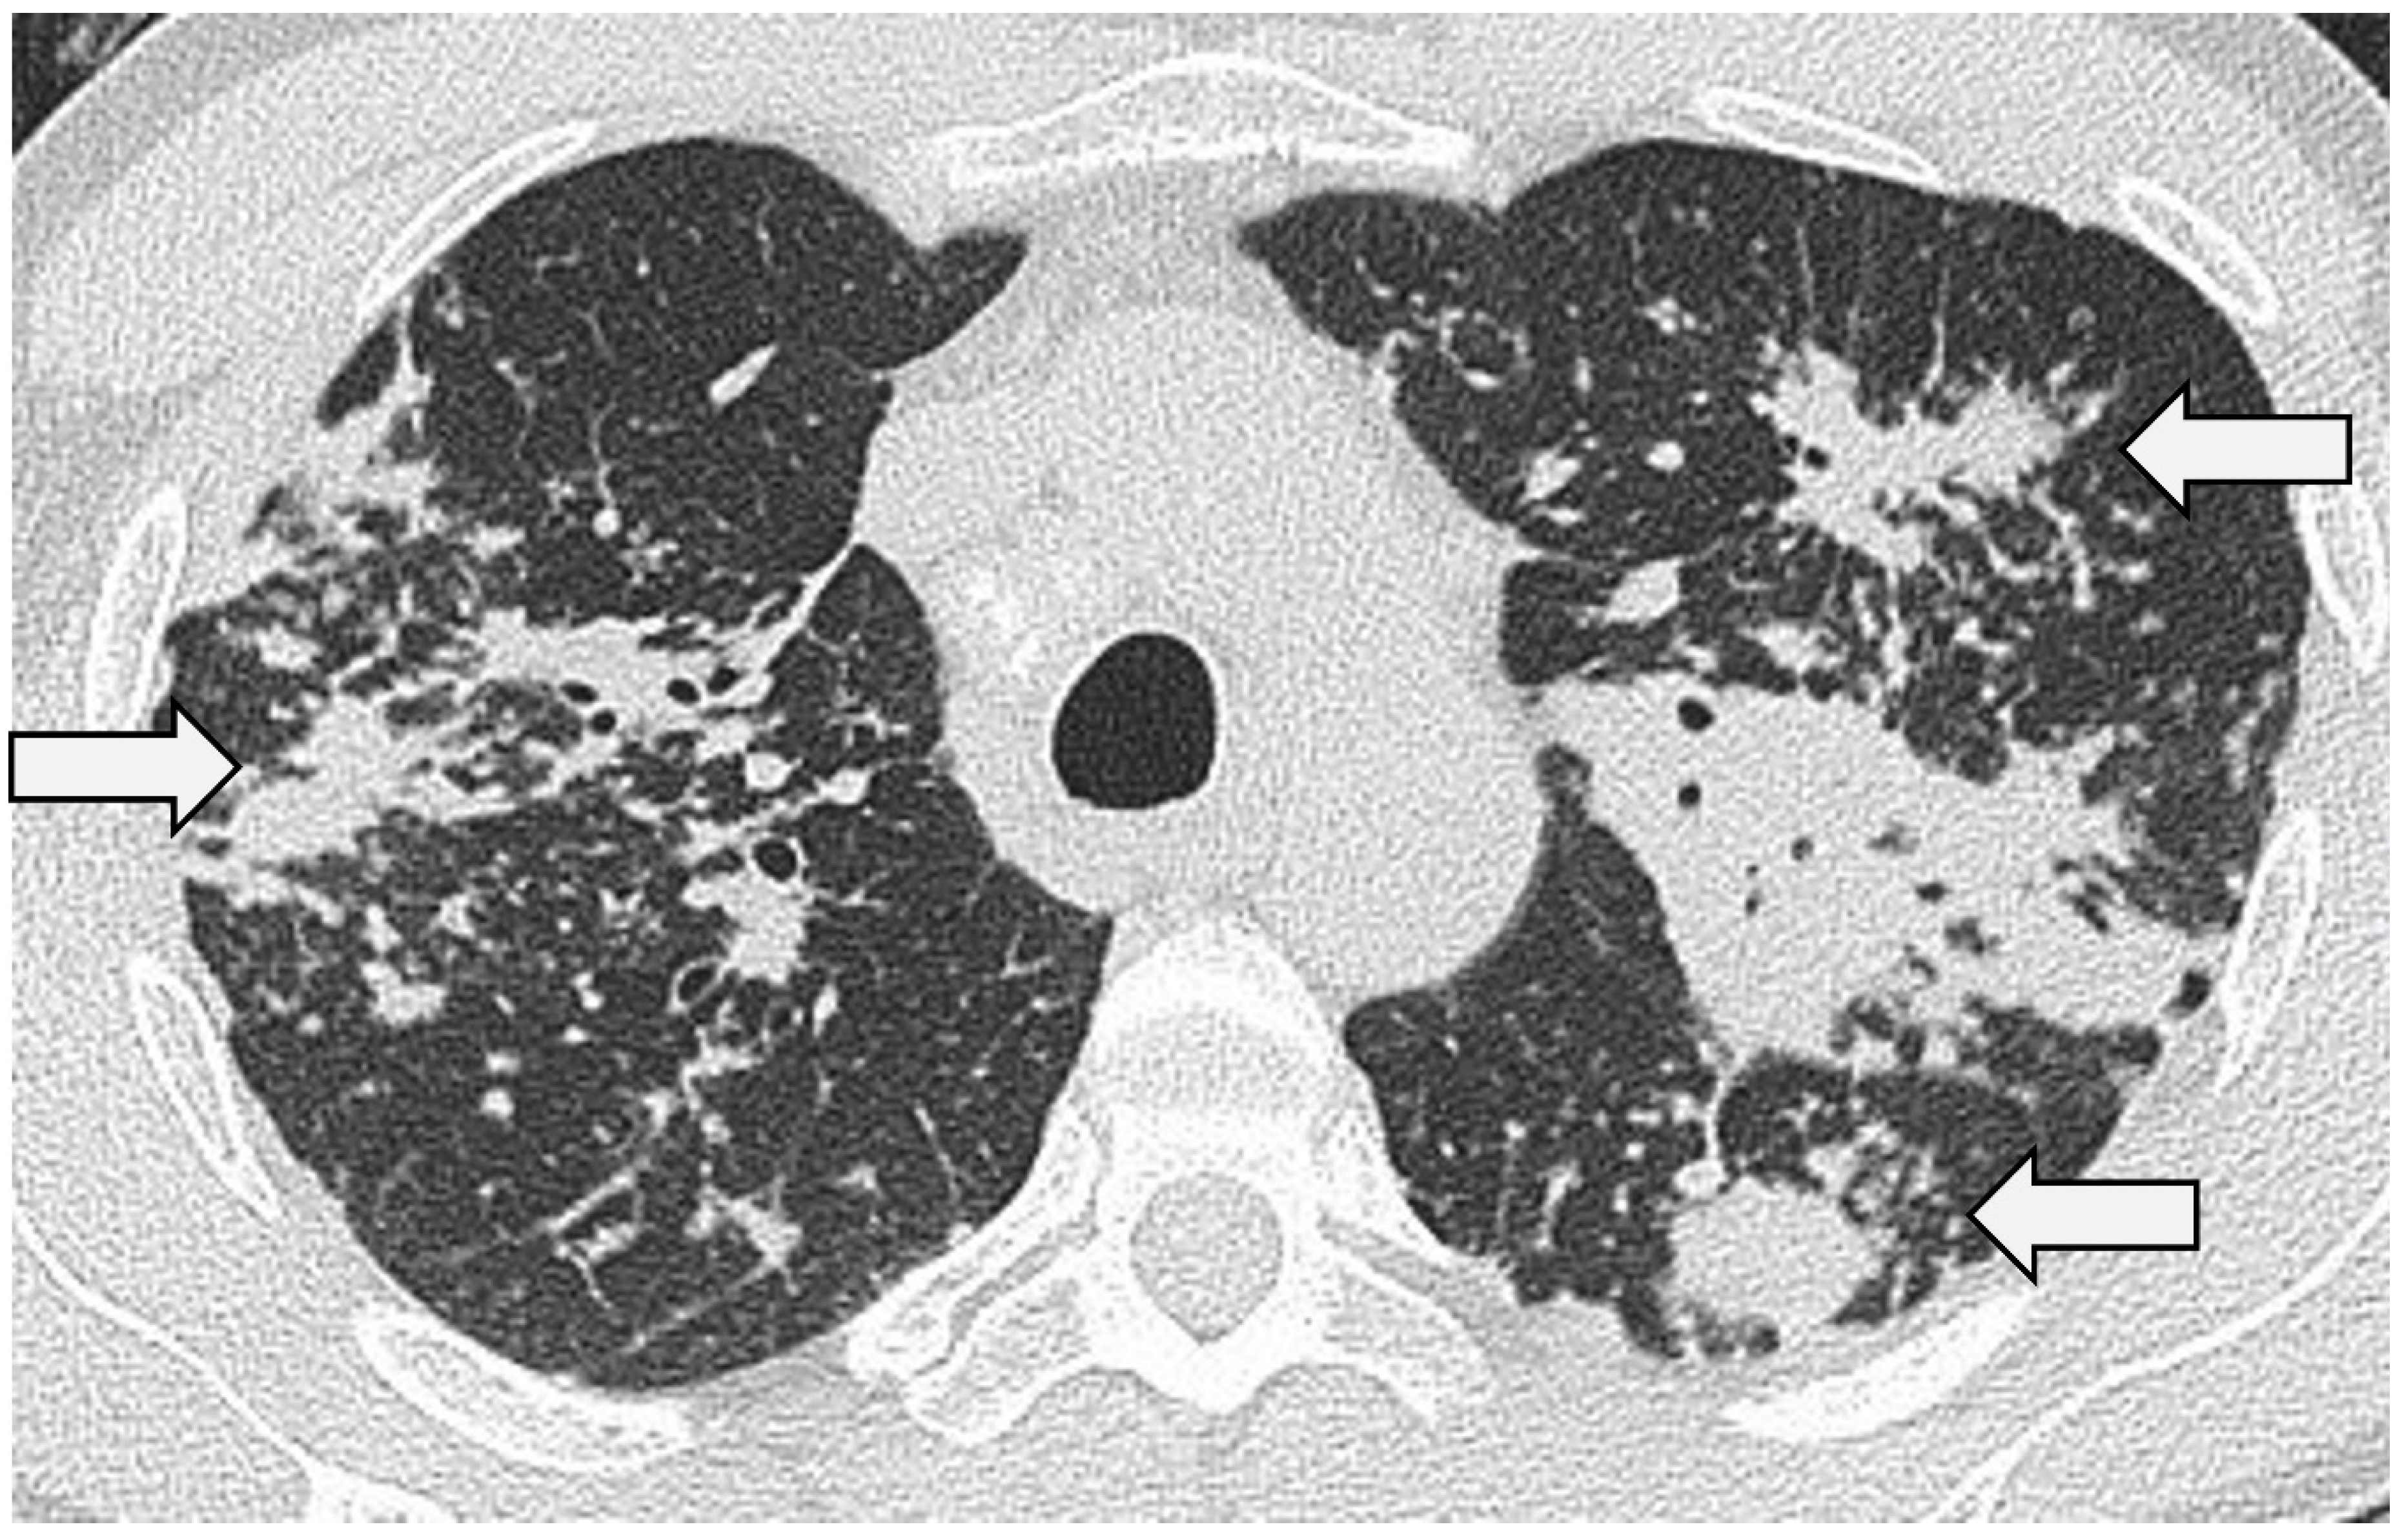

Figure 3.

Nodular sarcoidosis in a 46-year-old male patient. CT at the level of the aortic arch showing large nodules with surrounding micronodules (the ‘galaxy sign’) in both upper lobes (arrows).